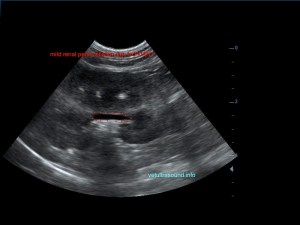

Ήπια ηπατομεγαλία με αύξηση της ηχογένειας του οργάνου, χωρίς παρουσία εστιακών αλλοιώσεων(pic.4). Πάχυνση του τοιχώματος της χοληδόχου κύστης με εικόνα βλεννοκήλης ( kiwi sign) και έντονη υπερηχογένεια στη περιοχή περί αυτού(pic.1&2). Ήπια διάταση της νεφρικής πυέλου, πιθανόν λόγω της πολυουρίας και πολυδιψίας(pic.3). Επασβέστωση στον οπίσθιο πόλο του δεξιού επινεφριδίου και αύξηση των διαστάσεών του(pic.6). Απουσία ασκιτικής συλλογής και παθολογικά διογκωμένων λεμφαδένων.